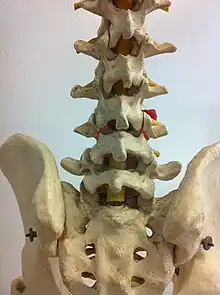

| Spondylolysis (wrong descriptions: the upper 3 arrows should be partes interarticulares) | |

Spondylolysis is a bony defect or fracture within the pars interarticularis of the vertebral arch in the spinal column. The vast majority of spondylolysis occur in the lumbar vertebrae, however it can also be seen in cervical vertebrae.[2] The lumbar vertebra consist of a body, pedicle, lamina, pars interarticularis, transverse process, spinous process and superior and inferior articular facets, which form joints that link the vertebrae together. When examining the vertebra, the pars interarticularis is the bony segment between the superior and inferior articular facet joints located anterior to the lamina and posterior to the pedicle. Separation of the pars interarticularis occurs when spondylolysis is present in the spinal column.[11]